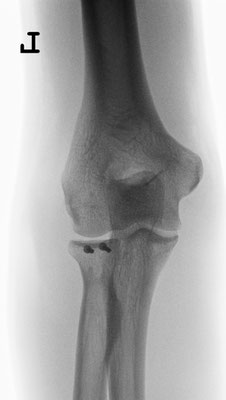

Radiusköpfchenbruch/Speichenköpfchenbruch

Einfache, sog. „Meißelbrüche“ des Speichenköpfchens können durch Minischrauben sehr stabil fixiert werden. Komplizierte Brüche müssen event. mit Miniplättchen verschraubt werden.

Bei ausgedehnter Zertrümmerung des Radiusköpfchens kann dieses mit Miniplättchen rekonstruiert werden oder sogar vollständig entfernt werden, ohne das die Funktion des Ellenbogens stark beeinträchtigt wird.

Häufiger kommt es allerdings zu zusätzlichen Bandverletzungen, insbesondere wenn der Ellenbogen luxiert war. In diesem Fall muss das Radiusköpfchen unbedingt erhalten werden, oder durch eine Radiusköpfchenprothese ersetzt werden. Durch die Wiederherstellung der knöchernen Führung wird die Stabilität des Ellenbogengelenkes wieder hergestellt. Zusätzlich wird der Bandapparat während der Operation genäht.